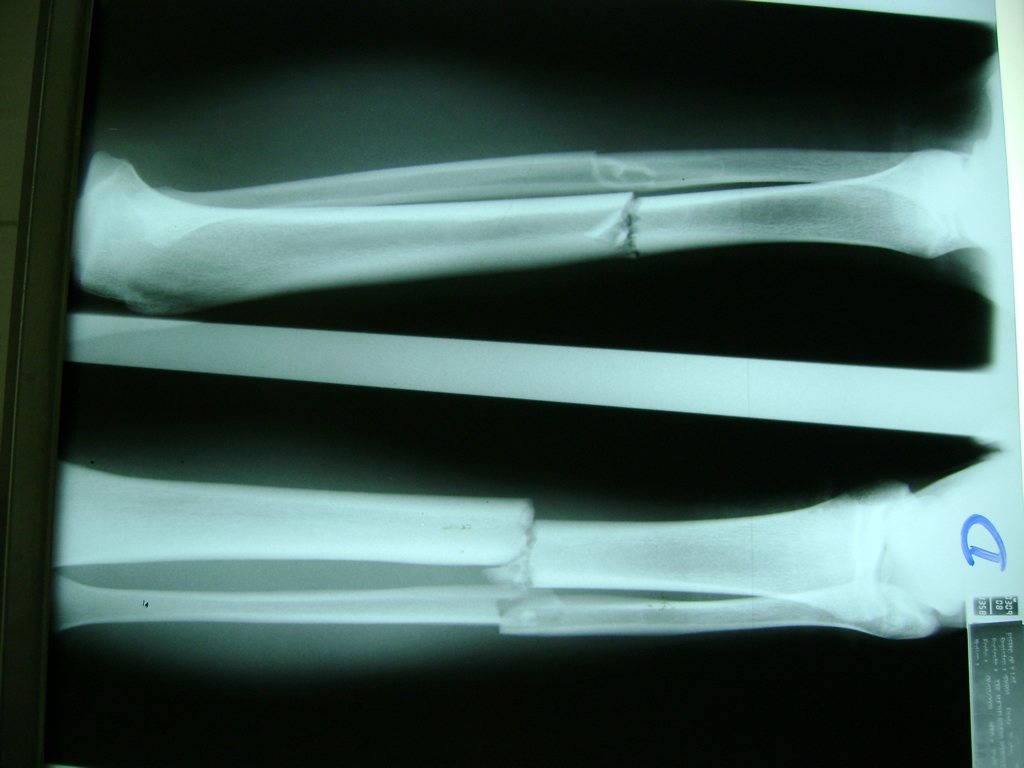

Cirugías de Codos - Perone y Tibia

Aunque cada uno de estos huesos puede fracturarse por separado, normalmente la rotura es una lesión que se produce de forma conjunta

La mayor parte de las roturas implican a la parte proximal del hueso (parte del hueso próximo a la rodilla) o a la parte distal (parte del hueso cerca del tobillo).

Debido a la fina cobertura de piel que recubre la tibia y el peroné, las fracturas generalmente son abiertas, es decir, el hueso roto rasga la piel, atravesándola. Las fracturas de tibia y peroné generalmente se producen por un fuerte impacto o torsión.